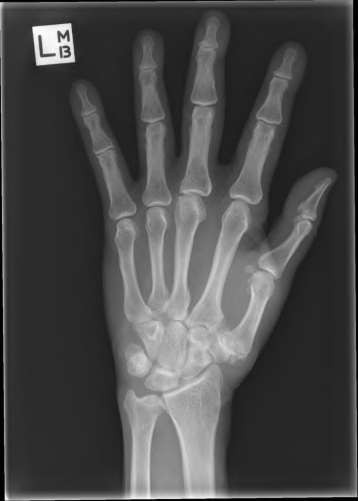

A 35-year-old woman reports wrist pain after a fall onto an outstretched hand. On exam, she has focal tenderness over the wrist snuffbox. A radiograph and CT image are shown in Figures A and B. What is the proper treatment of her injury?